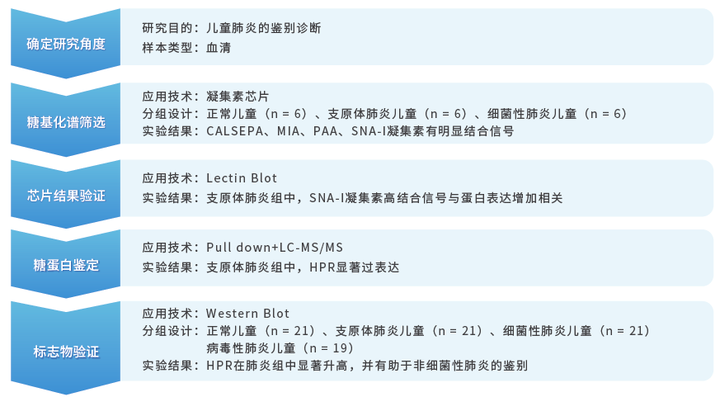

华盈生物-凝集素芯片标志物研发方案

| 凝集素芯片应用方向

| 凝集素芯片产品列表

| 凝集素芯片结果展示

》以GA-Lectin 70 芯片的70种凝集素检测结果为例

如芯片扫描图所示,BANLEC、BC2L-A、CALSEPA、GNA、HHA、NPA、PA-IIL和PALA凝集素与生物素标记的HRP孵育后呈强荧光信号。已知这八种凝集素可以和甘露糖进行特异性结合,且后续分别以梯度增加HRP/甘露糖浓度进行实验,结果显示,结合的荧光信号都随浓度的增加而减弱,进一步表明HRP蛋白中含有甘露糖结构(与芯片上的凝集素进行特异性结合)。另外, AAL和RS-FUC两种凝集素(与岩藻糖特异性结合)也显示出与HRP的强相互作用,表明HRP发生岩藻糖基化。

添加图片注释,不超过 140 字(可选)

》不同类型样品凝集素芯片实测结果展示

| 凝集素芯片应用案例

经典案例2:糖蛋白标志物的发现:儿童肺炎鉴别诊断

该研究的论文作者有多名来自华盈生物研发团队,成功应用了华盈生物新建立的凝集素芯片-标志物研发方案,综合了蛋白芯片与质谱两种蛋白组学技术,为复杂疾病的临床标志物开发提供了新的研究思路,具有借鉴意义。